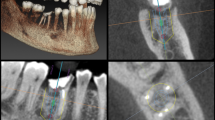

A total of 31 maxillary and 35 mandibular premolars were collected from patients undergoing orthodontic or periodontal treatment at the Dental Department of CGMH. The teeth were cleaned and scanned. The attained raw data of tooth structures were obtained as 2D images, which were assembled and converted into 3D reconstructions (Fig. 1). The 3D RSAs at the evaluated linear 2D CRRs were analyzed.

(A‒D): The views and estimated levels of a micro-CT scanned maxillary premolar. (A): maxillary premolar; (B): a sagittal view; (C): a–b: a line connecting the buccal and lingual CEJ, c–d: a line connecting the mesial and distal CEJ, e: the midpoint of a–b, f: the midpoint of c–d, g: the midpoint of e–f, representing the CEJ from a 2D perspective, and g–h: representing the 2D RL; (D): The CRRs were evaluated from 1:1 to 2:1. (E‒H): The views and evaluated levels of a micro-CT scanned mandibular premolar. (E): mandibular premolar; (F): the same as (B); (G): the same as (C); (H): The CRRs were evaluated from 1:1 to 2:1.